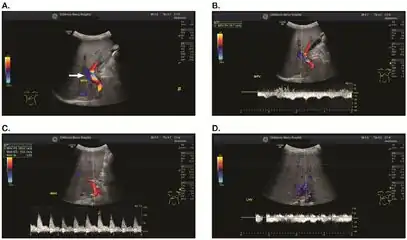

Doppler ultrasound of the liver is typically utilized to confirm or suggest the diagnosis. Common findings on liver doppler ultrasound include increased phasicity of portal veins with eventual development of portal flow reversal.

The liver is usually enlarged but maintained normal echogenicity. A liver biopsy is required for a definitive diagnosis.

a-d) Individual who developed VOD/SOS after HCT for acute myelogenous leukemia

a-d) Individual who developed VOD/SOS after HCT for acute myelogenous leukemia -